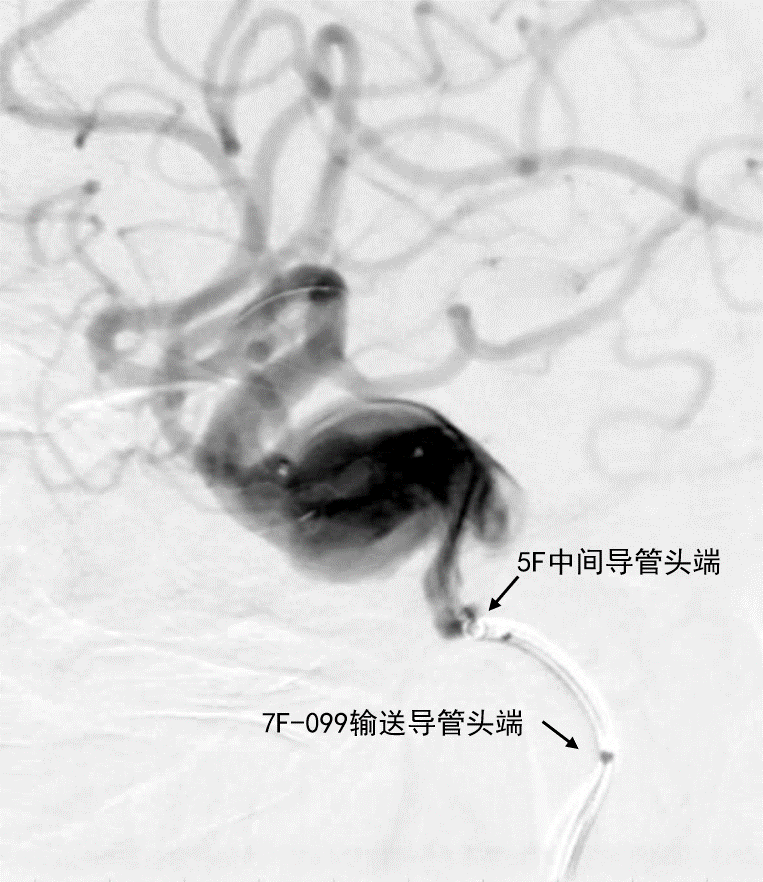

填入4枚大弹簧圈以稳定桥接支架。

填入4枚大弹簧圈

- 术后造影证实动脉瘤达大部分栓塞,载瘤动脉通畅

深瑞达7F输送导管正位造影

深瑞达7F输送导管侧位造影